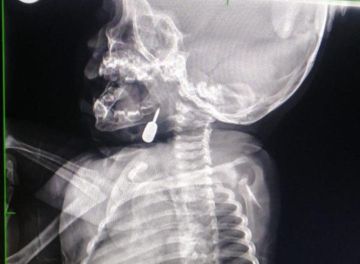

تمكّن أخصائي الأنف والأذن والحنجرة الدكتور محمود السبول من إجراء عملية فتح رغامى تعد الأولى من نوعها في مستشفى الملكة رانيا العبدالله، وقد تمت بنجاح.

وفي تدخل طبي عاجل، أنقذ الدكتور السبول حياة طفل يبلغ من العمر أحد عشر شهراً، بعد أن وصل إلى قسم الطوارئ وهو يعاني من حالة اختناق حادة نتيجة وجود جسم معدني عالق في منطقة الحنجرة. وقد تم استخراج الجسم بنجاح، مما أسهم في إنقاذ حياة الطفل.